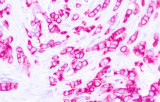

- Linfoma di Hodgkin classico: le cellule tumorali sono tipicamente CD30+ e spesso CD15+, con PAX5 debole e CD20 negativo nelle grandi cellule tumorali.